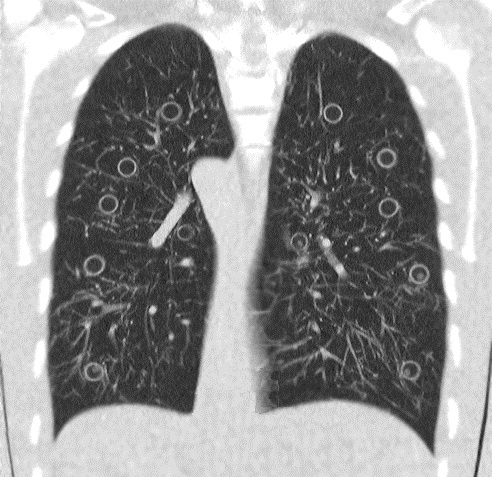

What is the real dose for “Ultra-Low-Dose Chest CT”?

Radiation dose is an increasing concern, especially in the chest, and this area allows very significant dose reduction, preserving diagnostic capability. The comparison with chest X-Rays is more and more valid.

Article: Dose estimation of ultra-low-dose chest CT to different sized adult patients